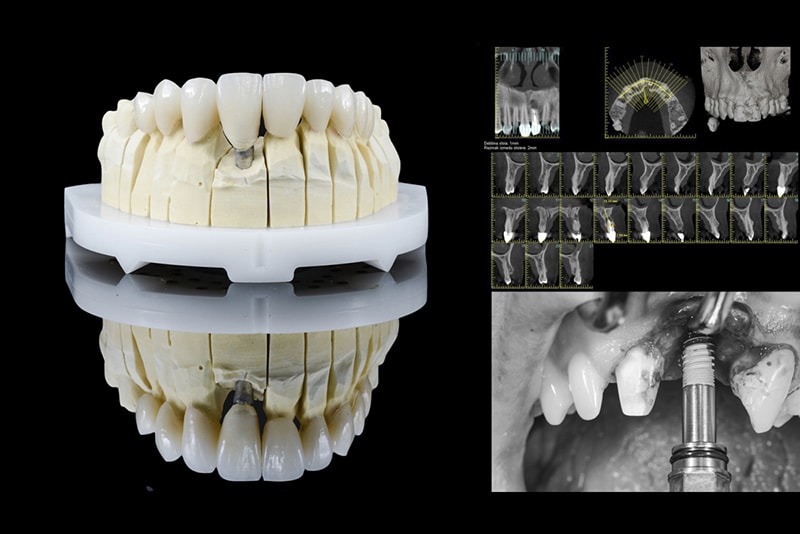

Complessa riabilitazione funzionale ed estetica

• l’estrazione del dente fratturato e il carico immediato della corona provvisoria su impianto dentale

• Corone in ceramica integrale su impianto dentale con le sovrastruttura individuale in ossido di zirconio

• Corone in ceramica integrale

Con la perdita dei denti nella zona estetica (parte anteriore) la sfida maggiore è il mantenimento dei tessuti molli, cioè la gengiva circostante. Per motivi di limitati risorse del tessuto, un piano preciso e prevedibile è di fondamentale importanza. Di grande importanza, nel caso di Suzana, era stabilire una correta funzione, con la quale come consequenza abbiamo ricevuto l’estetica di sorriso.